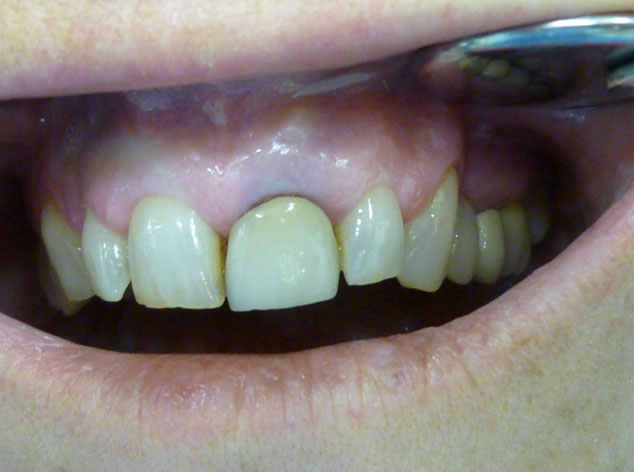

En estos casos han sido tratados con la filosofía de all-at-once, en la

misma sesión: